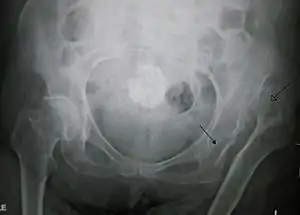

![]() | |

| Congenital dislocation of the left hip in an elderly person. Closed arrow marks the acetabulum, open arrow the femoral head. | |

Hip dysplasia diagnosed by ultrasound[40] and projectional radiography ("X-ray").[41] Ultrasound imaging is generally preferred at up to 4 months due to limited ossification of the skeleton.[39][notes 1]

Despite the widespread of ultrasound, pelvis X-ray is still frequently used to diagnose or monitor hip dysplasia or for assessing other congenital conditions or bone tumors.[42] The most useful lines and angles that can be drawn in the pediatric pelvis assessing hip dysplasia are as follows:[42] Different measurements are used in adults.[42]